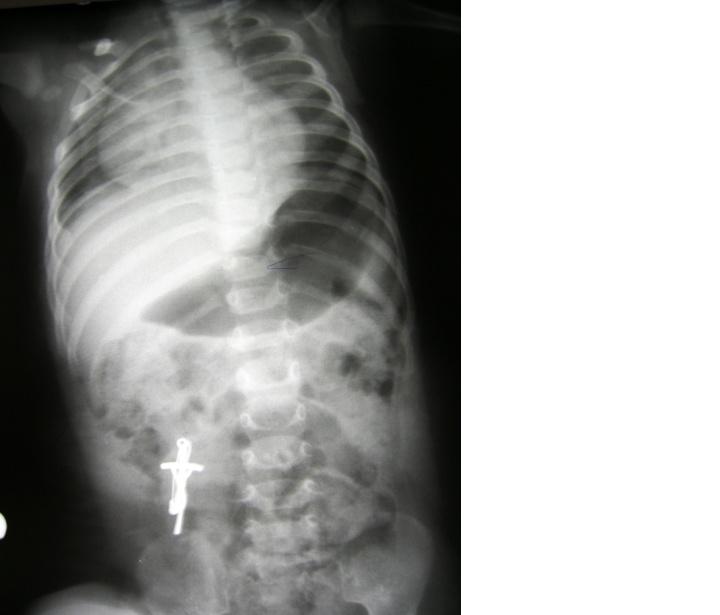

Noworodek płci żeńskiej, urodzony o czasie z Apgar 8, przekazany do oddziału intensywnej terapii noworodka w 2. dobie życia w ciężkim stanie ogólnym, zaintubowany z rozpoznaniem postępującej niewydolności oddechow -krążeniowej i podejrzeniem odmy opłucnowej lewostronnej. Wykonano zdjęcie RTG klatki piersiowej. Uwzględniając opisany gwałtowny przebieg kliniczny i

przedstawione RTG wymień najbardziej prawdopodobną przyczynę stanu dziecka: